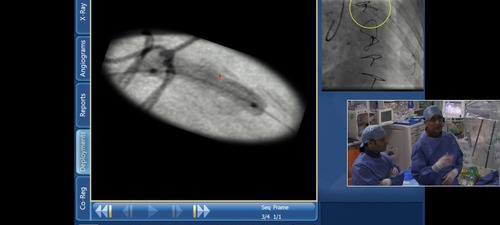

SyncVision lesion preparation was assessed

The panel discuss the interpreation of the SyncVision following ballooning of the proximal left anterior descending lesion

• SyncVision to Co-register IVUS and angiographic images

• SyncVision automated Stent Enchancement